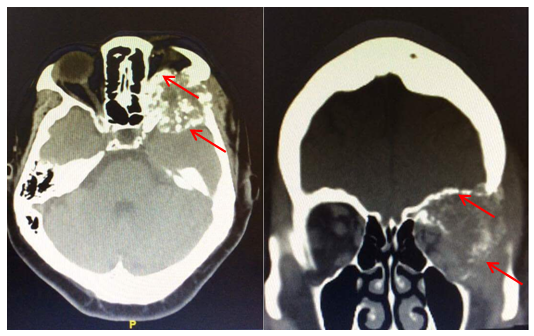

A computed tomography (CT) scan showed extensive lytic bone metastatic involvement of the orbital and temporal bones with mass effect on the left orbital contents, causing loss of the normal sphericity of the eyeball and proptosis (Figure 2). Biopsy with fine needle aspiration under ultrasound guidance: Demonstrated metastasis of papillary carcinoma of thyroid.